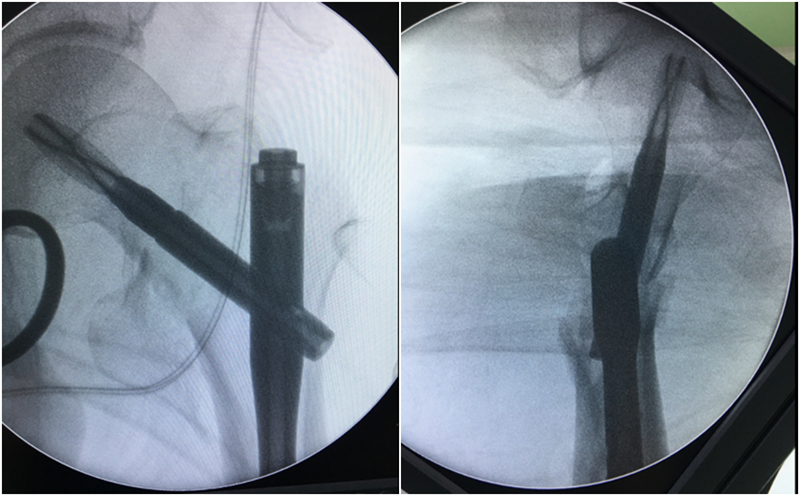

采用过度牵引方法是关键,先不要追求解剖复位。确定导针的位置以后,图A:将扩髓钻顶住近侧骨折块的外缘,开始扩髓;图B:扩髓钻打磨掉近侧骨折块外侧。

图8 A:将扩髓钻顶住近侧骨折块的外缘,开始扩髓;B:扩髓钻打磨掉近侧骨折块外侧。

然后放松牵引,解除过牵,骨折解剖复位以后再向远端扩髓、置钉,即可获得完美的复位固定。

图9